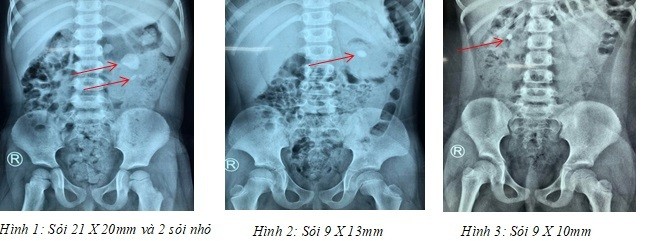

Bệnh viện tiếp nhận bệnh nhân từ một bệnh viện Nhi đồng tại TP.HCM, bệnh nhi gồm: bé V.N.K (3 tuổi, TP.HCM) có sỏi kích thước 21x20mm cùng 2 sỏi nhỏ ở thận trái, bé P.Đ.N.Y (7 tuổi, TP.HCM) có sỏi 9x10mm ở thận phải, N.T.T.N (6 tuổi, Cần Thơ) có sỏi 9x13mm ở trận trái.

Các ca phẫu thuật diễn ra trong hơn 1 giờ với sự phối hợp với các bác sĩ gây mê nhi từ Bệnh viện Nhi Đồng 1. Sau phẫu thuật, hình ảnh kiểm tra thấy thận đã sạch sỏi hoàn toàn. Ba bệnh nhi đã xuất viện trong tình trạng khỏe mạnh.